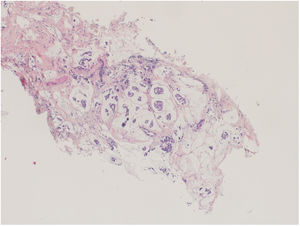

En el estudio anatomopatológico de la pieza quirúrgica se encontraron dos focos, de 15×10mm y 13×5mm, de carcinoma infiltrante residual G1 mucosecretor; el grado de respuesta a neoadyuvancia (sistema Miller Paine) fue G1 y la carga tumoral residual (MD Anderson) RCBII. Destaca la disminución del componente epitelial en relación con biopsia previa.

Su característica principal es la producción de mucina extracelular3. Existen dos tipos principales de CMS: el carcinoma mucosecretor puro (CMSP), más frecuente y con mejor pronóstico, y el carcinoma mucosecretor mixto (CMSM)3. Para ser considerado carcinoma mucosecretor puro este debe estar compuesto por al menos un 90% de mucina (tanto extracelular como intracelular). Asimismo, dependiendo del patrón de crecimiento, los CMSP se puede dividir en una variante hipocelular (CMSP-A) y una variante hipercelular (CMSP-B)3. Dentro de la variante hipocelular (CMSP-A) existen varios patrones de crecimiento (tubular, cribiforme, formando cordones o micropapilar). La variante hipercelular solo tiene un único patrón de crecimiento en nidos sólidos3. Los CMSM contienen menos del 90% de mucina y pueden expresar otros tipos histológicos. En nuestro caso, nos encontramos ante una variante de CMSP hipercelular.